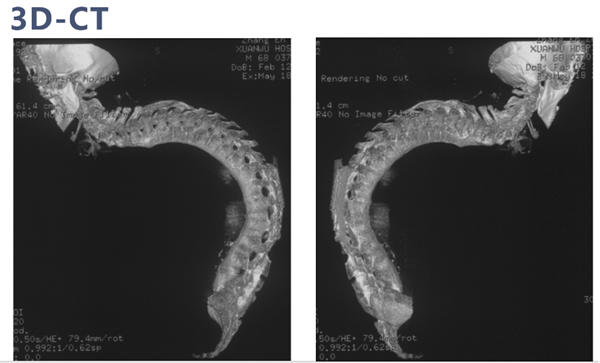

术前影像学检查

CT